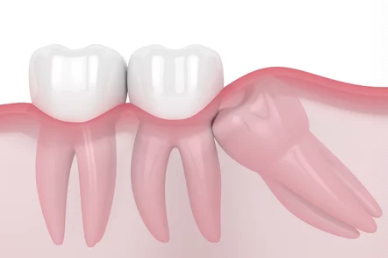

매복 사랑니란?

매복 사랑니는 턱뼈 안에서 완전히 나오지 못하거나 비정상적인 각도로 자란 사랑니를 말합니다. 이런 사랑니는 주변 치아를 밀거나 잇몸 염증, 통증 등을 유발할 수 있어 발치가 필요합니다.